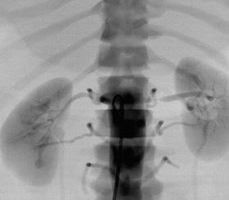

腎動脈介入手術(shù)模塊

可練習(xí)腎動脈支架手術(shù)的完整過程:造影診斷、導(dǎo)絲通過、導(dǎo)引導(dǎo)管的放置、保護(hù)傘的放置、預(yù)擴張、自擴張支架放置、后擴張、以及再造影等